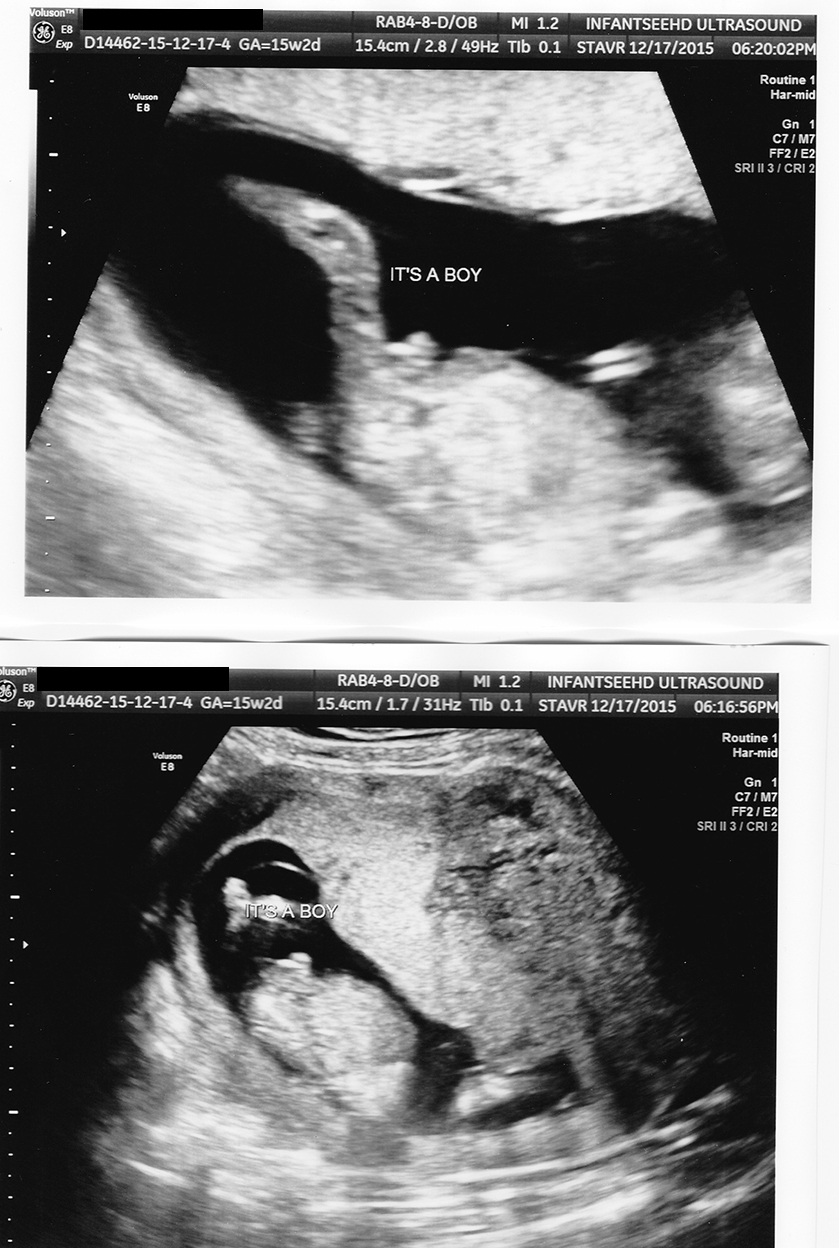

I went to an early ultrasound service and I'm now terrified the gender is going to change at my 20 week appointment. I had the tech write it down and put the images in an envelope so he couldn't explain. Please reassure me this looks blue! :nails:

Attachment 28970

Attachment 28971